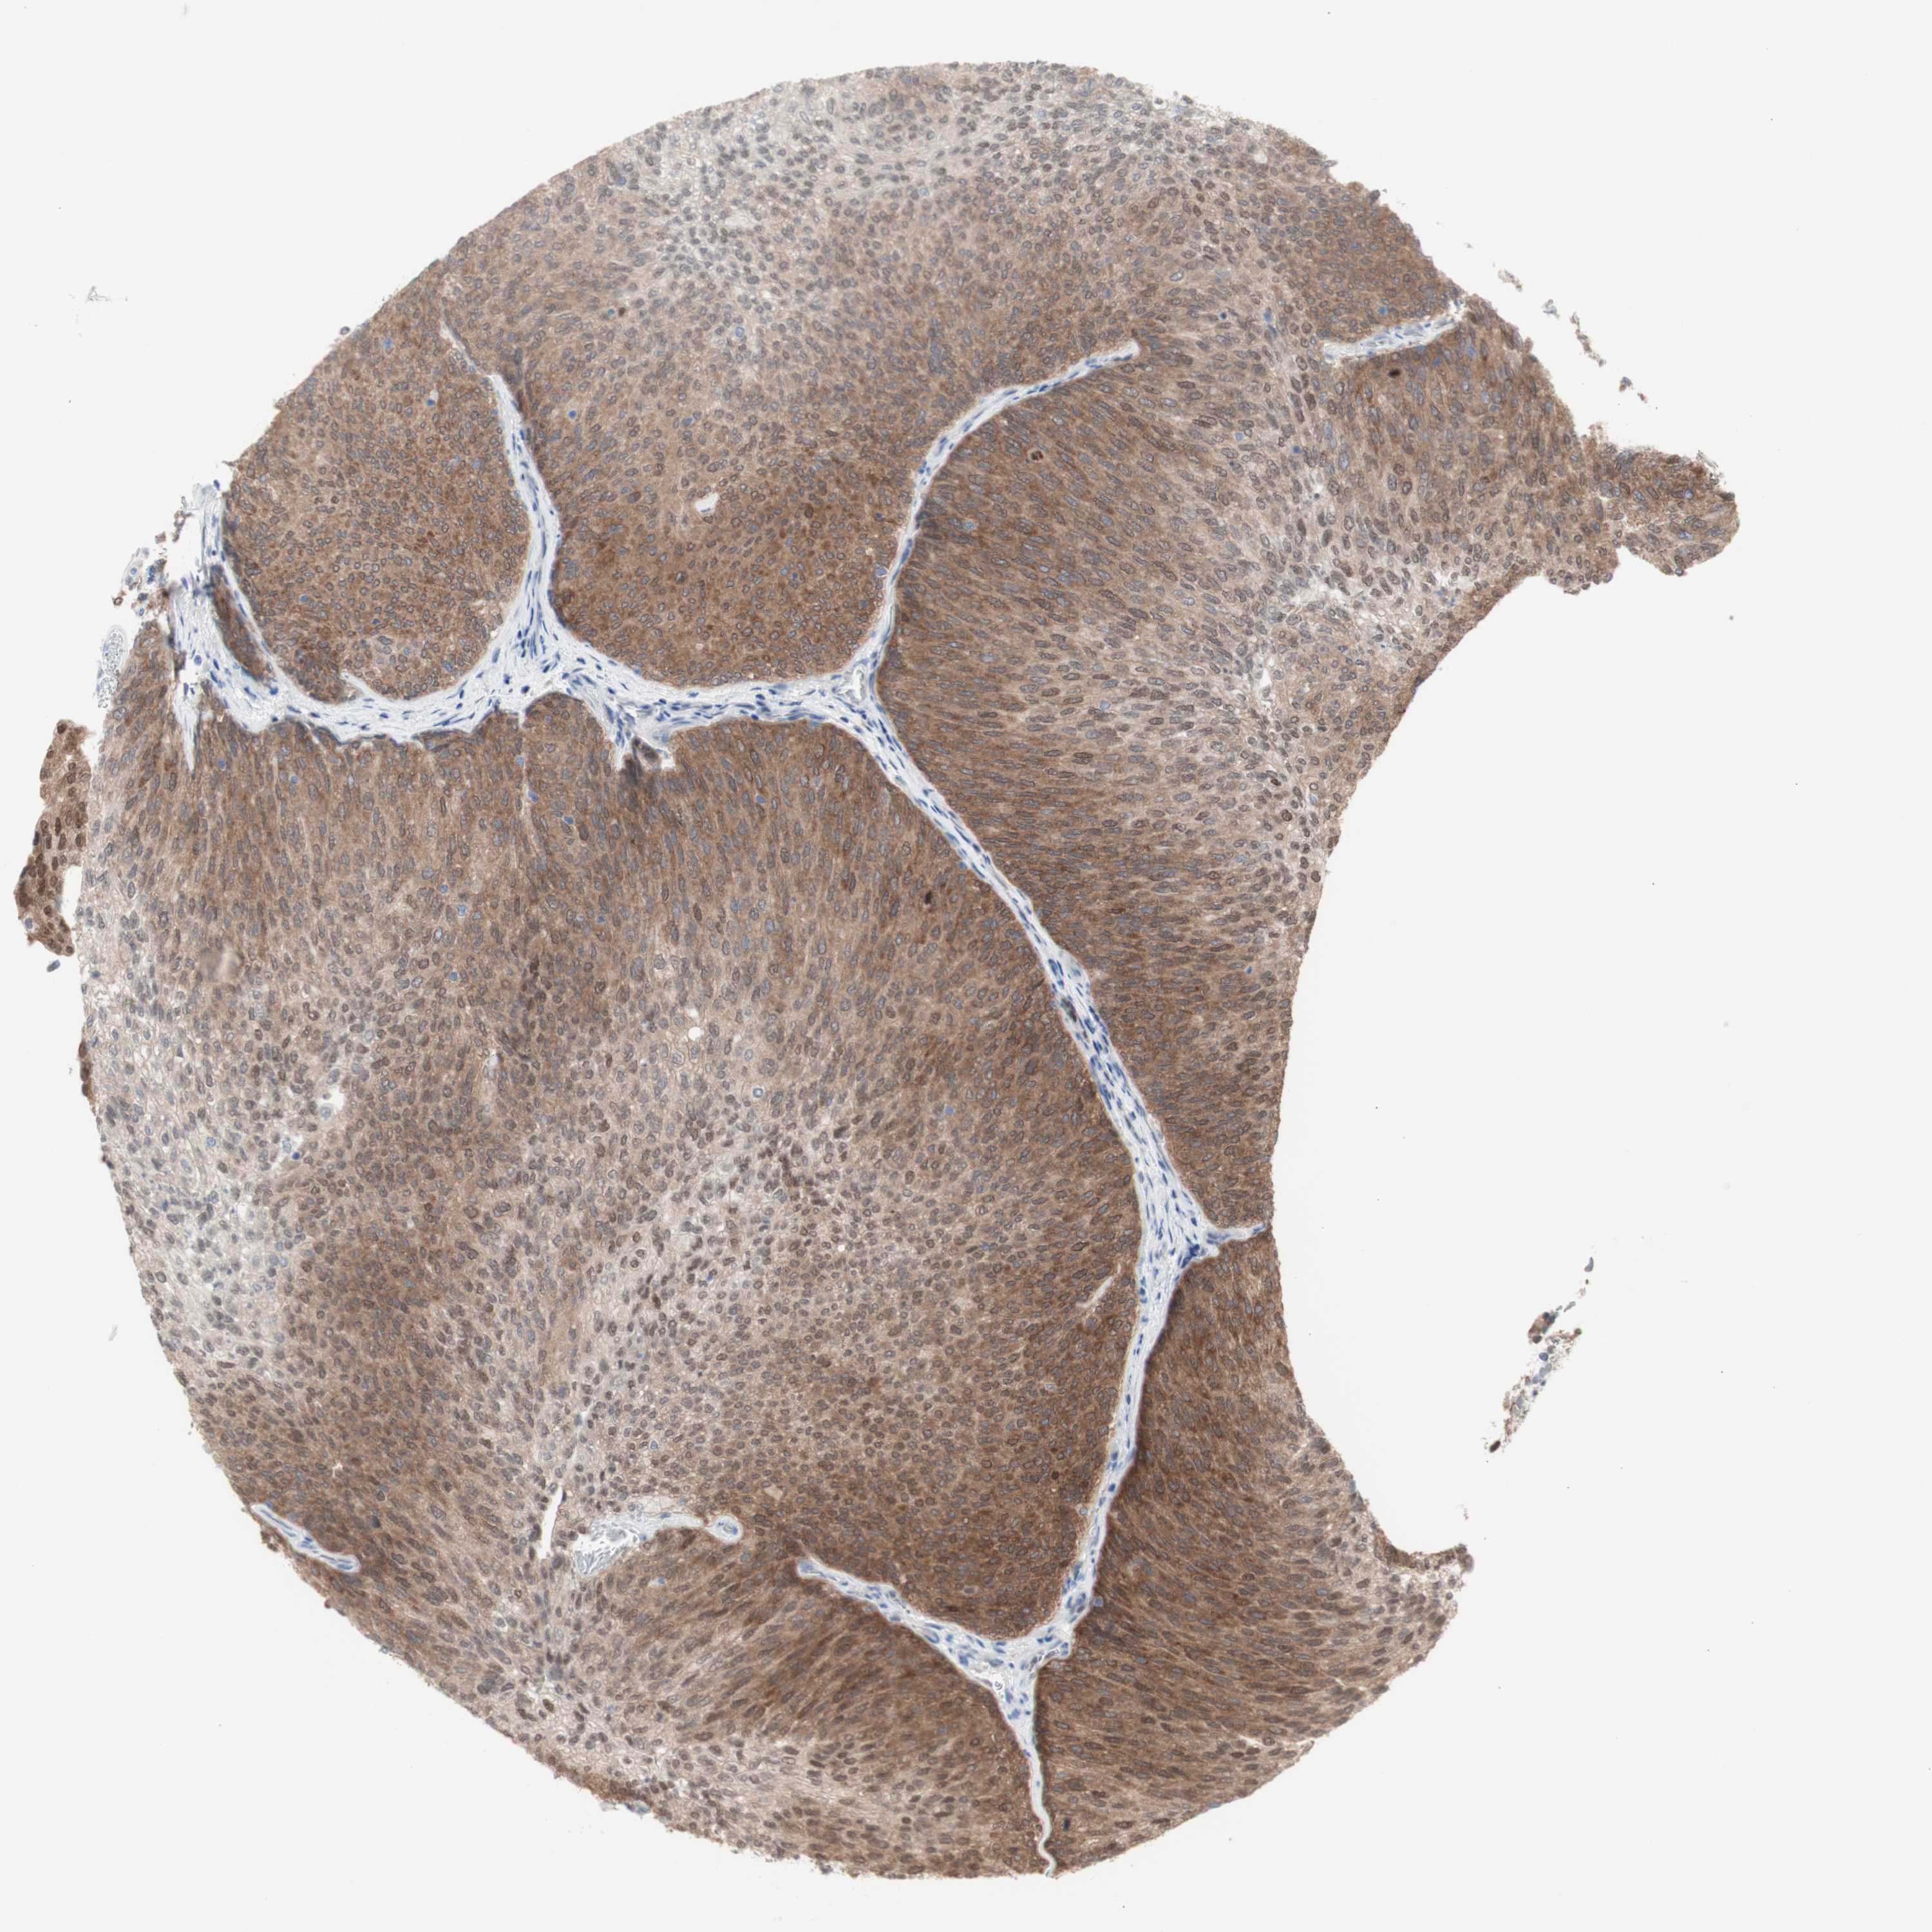

UROTHELIAL CANCER - Protein expressioni

A mouse-over function shows sample information and annotation data. Click on an image to view it in a full screen mode. Samples can be filtered based on level of antibody staining by selecting one or several of the following categories: high, medium, low and not detected. The assay and annotation is described here.

Note that samples used for immunohistochemistry by the Human Protein Atlas do not correspond to samples in the TCGA dataset.

Antibody stainingi

Antibody staining in the annotated cell types in the current human tissue is reported as not detected, low, medium, or high, based on conventional immunohistochemistry profiling in selected tissues. This score is based on the combination of the staining intensity and fraction of stained cells.

Each image is clickable and will lead to virtual microscopy that enables deeper exploration of all samples and also displays staining intensity scores, fraction scores and subcellular localization as well as patient and tissue information for each sample.

Antibody HPA005525

Antibody HPA064708

Antibody CAB012459

Staining

High

Medium

Low

Not detected

Intensity

Strong

Moderate

Weak

Negative

Quantity

>75%

75%-25%

<25%

None

Location

Nuclear

Cytoplasmic/membranous

Cytoplasmic/membranous,nuclear

Urothelial carcinoma, High grade

Urothelial carcinoma, Low grade

Urothelial carcinoma, NOS